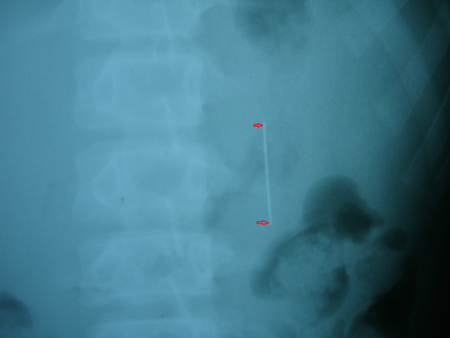

Chiều ngày 21/11, cháu Nguyễn Phan Duy Phước (13 tuổi, trú xã Đăk La, Đắk Hà, Kon Tum) trong lúc vừa kết vòng hoa vừa ngậm chiếc kim khâu dài 6cm, do vừa làm vừa nói chuyện nên Phước đã nuốt phải chiếc kim vào dạ dày. Ngay lập tức, Phước được gia đình đưa vào nhập viện ĐK Kon Tum.

| Chiếc kim cuối cùng đã đi ra khỏi cơ thể theo đường tự nhiên | Kết quả chụp X Quang cho thấy, chiếc kim may dài 6cm nằm dọc trong dạ dày cháu Phước. Do dị vật là chiếc kim dài, sắc nhọn nên diễn biến rất khó lường, có thể có nhiều biến chứng.

Nên để đưa dị vật ra ngoài, các bác sĩ quyết định áp dụng biện pháp hướng dẫn cho bệnh nhân ăn nhiều chất xơ sẽ khiến cho phân chắc lại, từng bước “dìu” chiếc kim ra ngoài theo đường bài tiết, hạn chế tai biến.

Tuy vậy, các bác sĩ vẫn luôn sẵn sang để mổ cho bệnh nhân nếu dị vật di chuyển không như ý đồ ban đầu.

Sau một thời gian kiên trì với liệu pháp ban đầu, cuối cùng chiếc kim đã di chuyển dọc theo thành ruột non và được thải an toàn ra ngoài.